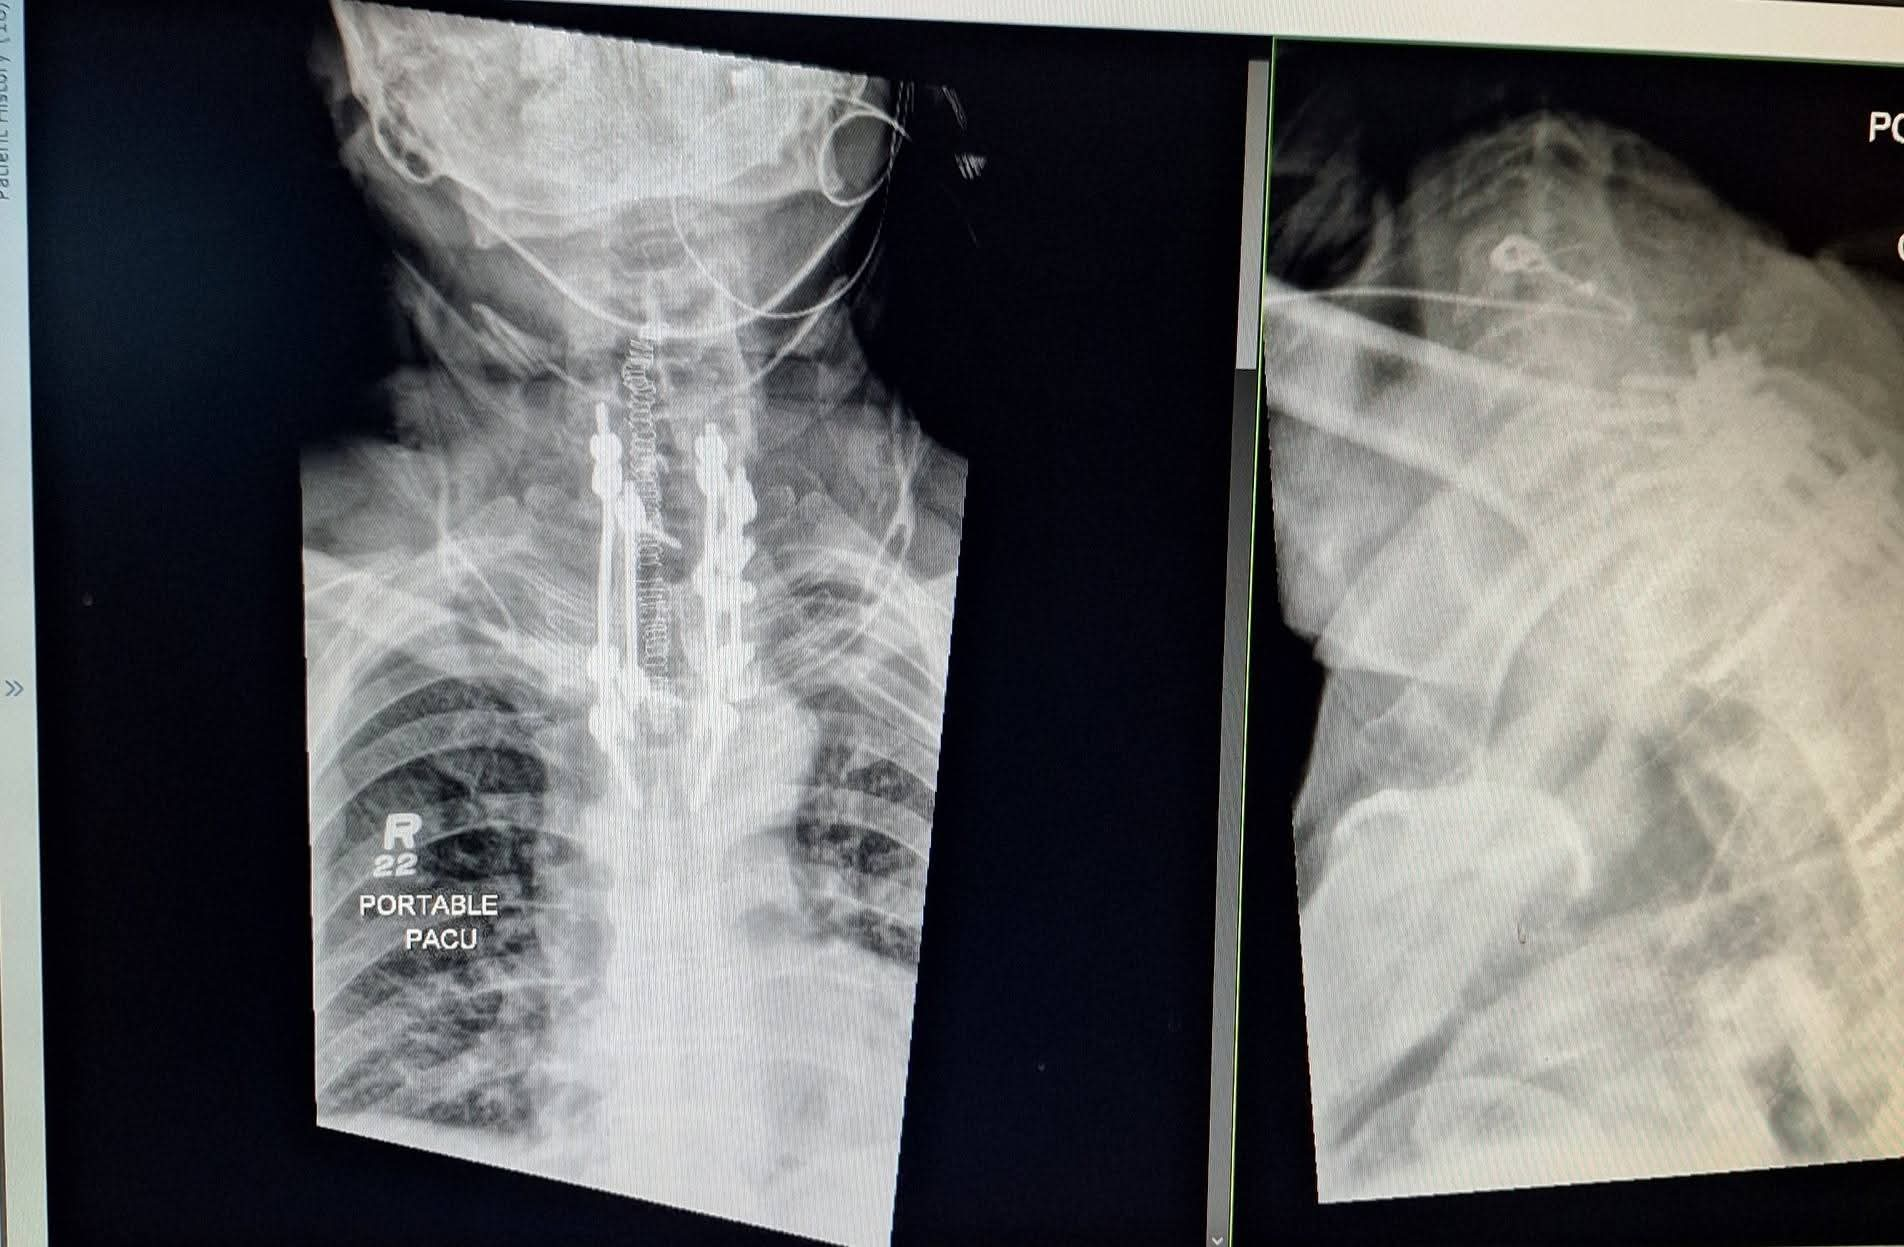

We are reaching out with heavy hearts and unwavering faith as Terry faces Metastatic Renal Cell Carcinoma, an aggressive form of kidney cancer that has already spread beyond the kidney. Terry is currently recovering from thoracic spine surgery where the surgeon fused C5-7 and rebuilt around T1, 2, and 3. This surgery was performed to de-bulk a lemon-sized tumor that was choking out his spinal cord and causing severe bone damage. From recent scans (7/21), we learned that the tumor is still very large and has potentially grown since surgery.